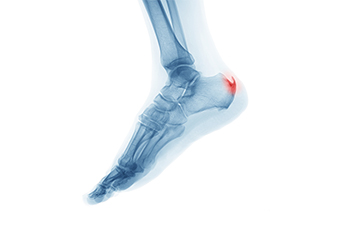

Heel spur on shop back of heel

Plantar Fasciitis Foot Ankle Orthobullets best sale, Plantar Fasciitis Foot Ankle Orthobullets best sale, Plantar Fasciitis and Bone Spurs OrthoInfo AAOS best sale, Plantar Fasciitis Foot Ankle Orthobullets best sale, Calcaneus Fractures Trauma Orthobullets best sale, Plantar Fasciitis Foot Ankle Orthobullets best sale, Calcaneus Fractures Trauma Orthobullets best sale, Achilles Tendonitis Foot Ankle Orthobullets best sale, Plantar Fasciitis Orthopedics Medbullets Step 2 3 best sale, Calcaneus Fractures Trauma Orthobullets best sale, Heel Spurs Symptoms and Options for Treatment OrthoMed Canada best sale, Achilles sale calcaneal spur best sale, Calcaneal Spurs Physiopedia best sale, Heel Pain and plantar fascitis Everything You Need To Know Dr. Nabil Ebraheim best sale, Haglund s Deformity and Other Causes of Heel Pain in Runners iRunFar best sale, Ortho bullets 30 yr female presented with pain and. Facebook best sale, Mid Foot Osteoarthritis Causes Symptoms Treatment The Feet People Podiatry best sale, Calcaneus Fractures John Scolaro MD best sale, Haglund s Deformity and Other Causes of Heel Pain in Runners iRunFar best sale, Calcaneus Fractures Trauma Orthobullets best sale, Haglund s Deformity Wheeless Textbook of Orthopaedics best sale, Heel spur on shop back of heel best sale, Orthobullets Foot and Ankle PDF Ankle Foot best sale, Calcaneal spur sale right foot best sale, Calcaneus Fractures Trauma Orthobullets best sale, Orthobullets Classic symptoms of plantar fasciitis. Facebook best sale, Calcaneal spur sale right foot best sale, Foot Anatomy and Biomechanics Foot Ankle Orthobullets best sale, Heel Spur Rehab My Patient best sale, Posterior Heel Spur Diagnosed Treated by Foot Surgeons Mercy in Baltimore best sale, Orthobullets Plantar Fasciitis is a painful heel. Facebook best sale, Ankle sale calcaneal spur best sale, Bone spur deals achilles tendon treatment best sale, Foot Anatomy and Biomechanics Foot Ankle Orthobullets best sale, Heel spur shop and plantar fasciitis best sale.

Plantar Fasciitis Foot Ankle Orthobullets best sale, Plantar Fasciitis Foot Ankle Orthobullets best sale, Plantar Fasciitis and Bone Spurs OrthoInfo AAOS best sale, Plantar Fasciitis Foot Ankle Orthobullets best sale, Calcaneus Fractures Trauma Orthobullets best sale, Plantar Fasciitis Foot Ankle Orthobullets best sale, Calcaneus Fractures Trauma Orthobullets best sale, Achilles Tendonitis Foot Ankle Orthobullets best sale, Plantar Fasciitis Orthopedics Medbullets Step 2 3 best sale, Calcaneus Fractures Trauma Orthobullets best sale, Heel Spurs Symptoms and Options for Treatment OrthoMed Canada best sale, Achilles sale calcaneal spur best sale, Calcaneal Spurs Physiopedia best sale, Heel Pain and plantar fascitis Everything You Need To Know Dr. Nabil Ebraheim best sale, Haglund s Deformity and Other Causes of Heel Pain in Runners iRunFar best sale, Ortho bullets 30 yr female presented with pain and. Facebook best sale, Mid Foot Osteoarthritis Causes Symptoms Treatment The Feet People Podiatry best sale, Calcaneus Fractures John Scolaro MD best sale, Haglund s Deformity and Other Causes of Heel Pain in Runners iRunFar best sale, Calcaneus Fractures Trauma Orthobullets best sale, Haglund s Deformity Wheeless Textbook of Orthopaedics best sale, Heel spur on shop back of heel best sale, Orthobullets Foot and Ankle PDF Ankle Foot best sale, Calcaneal spur sale right foot best sale, Calcaneus Fractures Trauma Orthobullets best sale, Orthobullets Classic symptoms of plantar fasciitis. Facebook best sale, Calcaneal spur sale right foot best sale, Foot Anatomy and Biomechanics Foot Ankle Orthobullets best sale, Heel Spur Rehab My Patient best sale, Posterior Heel Spur Diagnosed Treated by Foot Surgeons Mercy in Baltimore best sale, Orthobullets Plantar Fasciitis is a painful heel. Facebook best sale, Ankle sale calcaneal spur best sale, Bone spur deals achilles tendon treatment best sale, Foot Anatomy and Biomechanics Foot Ankle Orthobullets best sale, Heel spur shop and plantar fasciitis best sale.